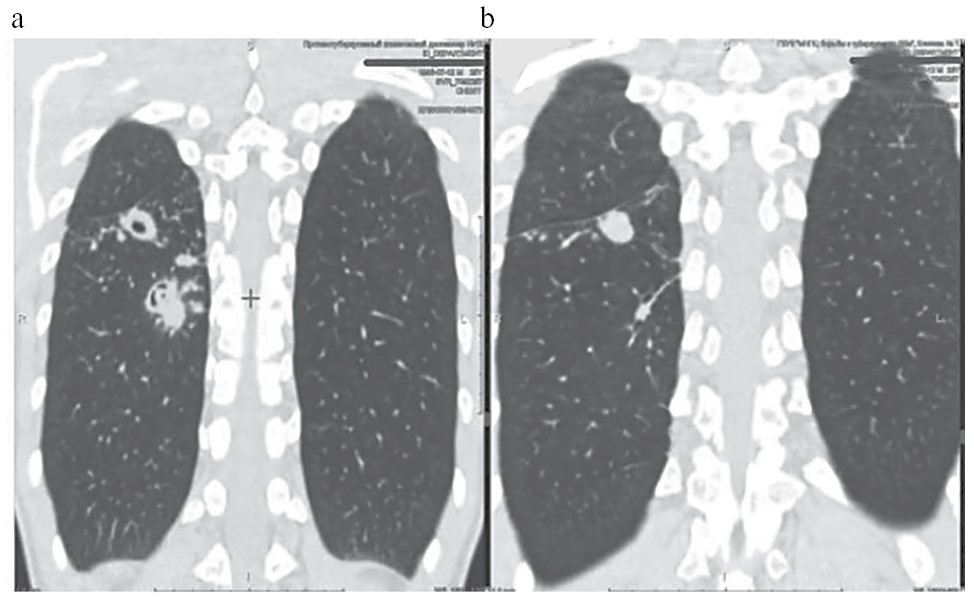

По данным КТ с энтерографией выявлены воспалительные изменения стенок илеостомы (рис. 3), ободочной кишки (рис. 4) и мезентериальная лимфаденопатия (рис. 5).

Рис. 3. КТ-энтерография. Картина воспалительных изменений стенок илеостомы.

Fig. 3. CT-enterography. Inflammatory changes in the walls of the ileostomy.